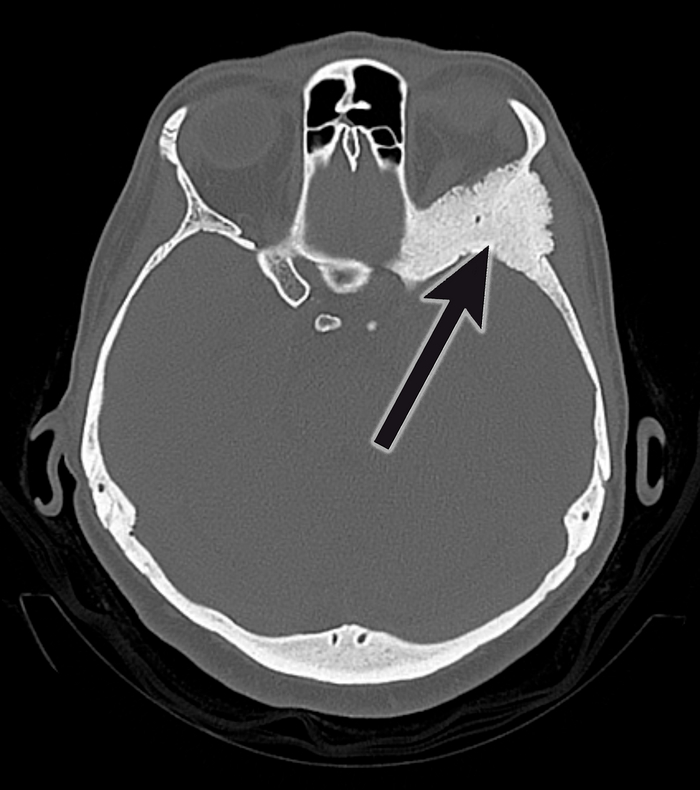

Операция включала в себя радикальное удаление опухоли, а также восстановление нормальной анатомии орбиты для обеспечения правильного положения глаз. Особое внимание нейрохирурги уделили минимизации косметических дефектов и сохранению симметрии лица.  Во время операции команда врачей использовала инновационную технологию костной пластики краниоорбитальной области с помощью индивидуального импланта.

Операция проведена совместно с коллегами из Института нейрохирургии имени Бурденко, так как именно в этом центре была разработана технологию индивидуальной краниопластики. В ходе планирования операции использовалась программа, которая позволяет создать зеркальное отображение «здоровой» стороны черепа на пораженной опухолью области.  Затем на основе этой виртуальной 3D-модели создали пресс-формы с помощью 3D-печати. Во время операции эти пресс-формы использовались для создания индивидуального импланта из костного цемента непосредственно в операционной.

«Благодаря применению данной технологии удалось избежать грубых косметических дефектов. Очень важно, что пациентка быстро восстановилась после операции и вернулась к привычной жизни, не испытывая никаких проблем с внешностью», — отметил нейрохирург Центра мозга Семён Мельченко.

КТ после операции